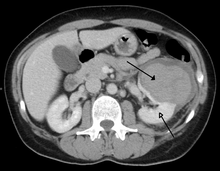

Abdominal trauma resulting in a right kidney contusion (open arrow) and blood surrounding the kidney (closed arrow) as seen on CT. | |

Kidneys

The kidneys may also be injured; they are somewhat but not completely protected by the ribs.[7] Kidney lacerations and contusions may also occur.[13] Kidney injury, a common finding in children with blunt abdominal trauma, may be associated with bloody urine.[13] Kidney lacerations may be associated with urinoma or leakage of urine into the abdomen.[6] A shattered kidney is one with multiple lacerations and an associated fragmentation of the kidney tissue.[6]